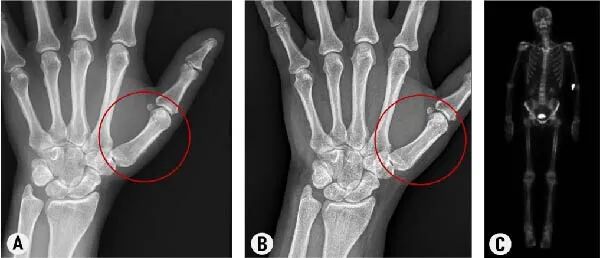

甲状腺肢端病:手指 / 脚趾肿胀、杵状变,手足关节疼痛僵硬,甚至无法穿正常鞋子,影像学检查显示掌骨、指骨骨膜反应明显(提示新骨形成)。

影像学验证:手部 X 线显示骨膜反应明显减轻,骨扫描提示异常骨活动消失;